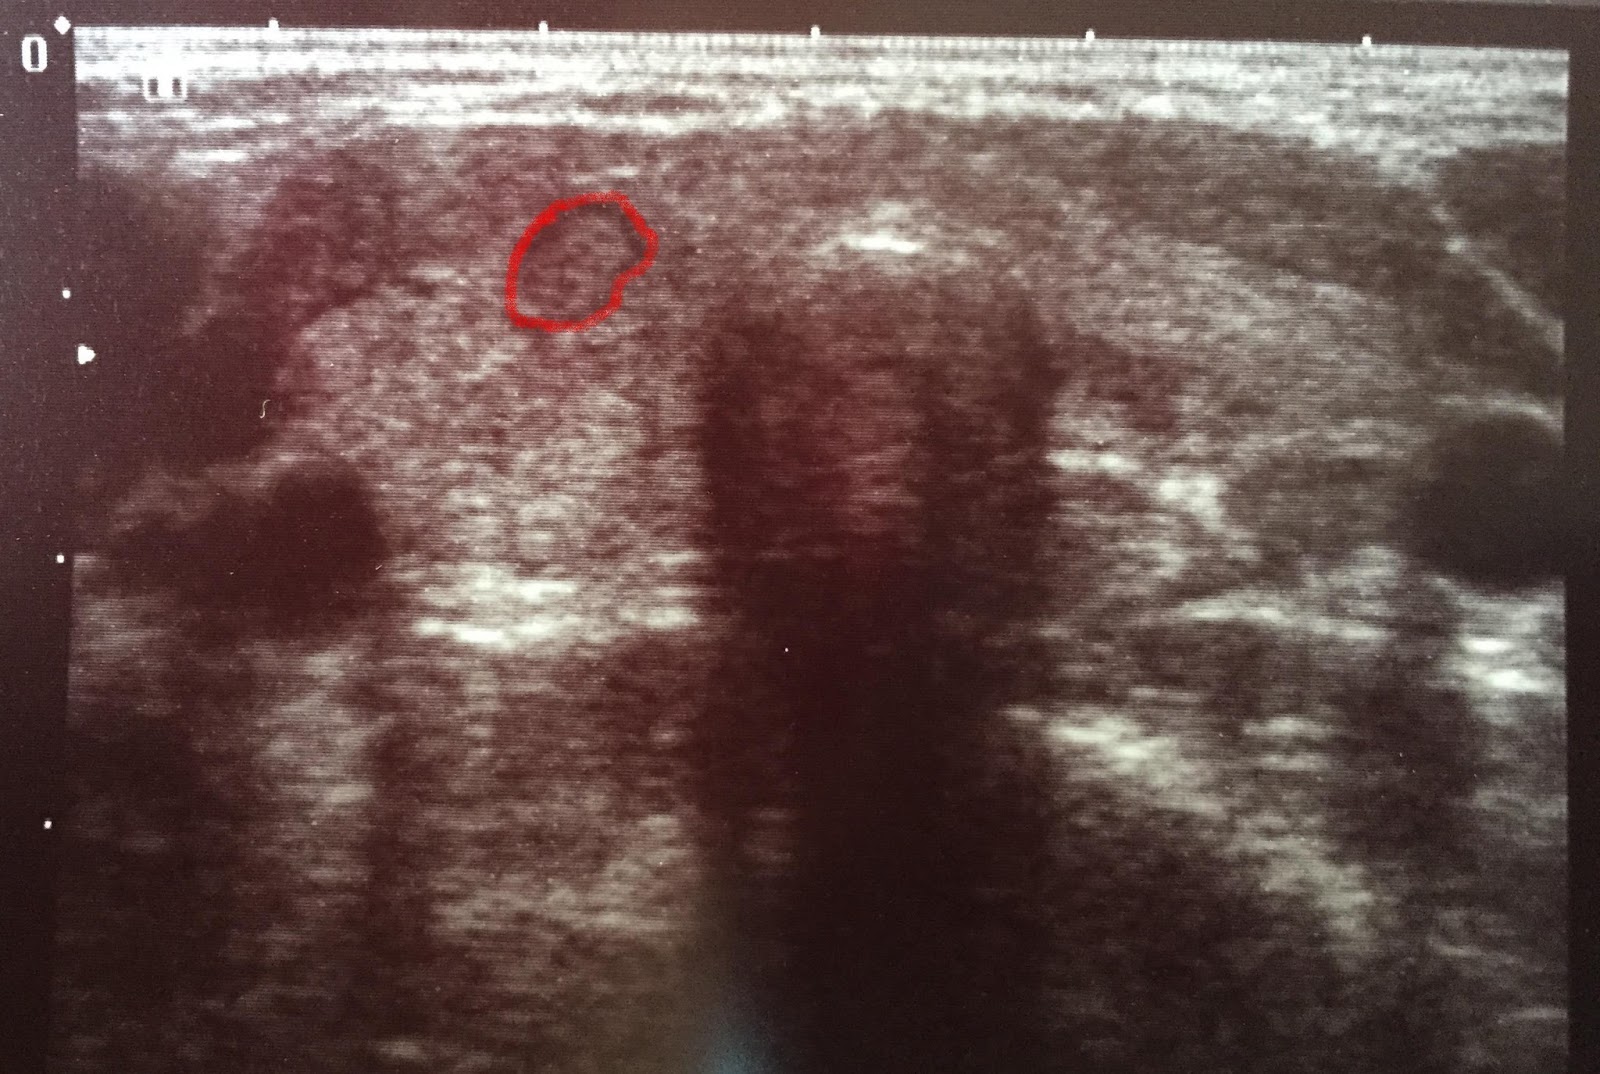

| guzek tarczycy |

| ten sam guzek, ale zaznaczony na czerwono |